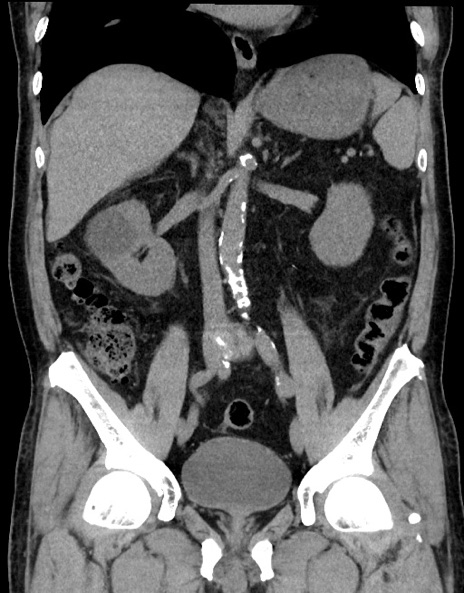

症例15(冠状断像)

【症例】70歳代男性

【主訴】腹痛

【現病歴】今朝から腹痛あり。全体的に痛い。特に左上の方。排ガスが今日はない。冷や汗が出る。

【既往歴】直腸癌術後

【身体所見】左側腹部〜上腹部に圧痛あり。腹膜刺激症状明らかなではない。軽度反跳痛。左下腹部に術後瘢痕あり。

【データ】WBC 7700、CRP 0.02